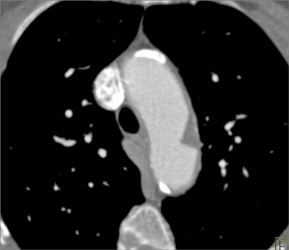

Diagnosis

CAM -cystic Adenomatoid Malformation